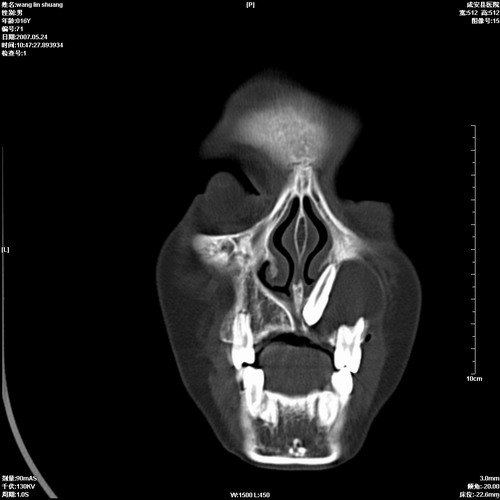

病人,男 16岁,鼻旁右肿胀,其余无不适感,ct图片

1、典型右侧根尖囊肿。

2、双侧上颌窦、筛窦、蝶窦炎

1\\左侧上颌骨含牙囊肿

2\\两上颌窦炎

右侧上颌骨含牙囊肿.双侧上颌窦炎症.

右侧上颌骨含牙囊肿.双侧上颌窦、蝶窦右侧炎症.

1、左侧上颌骨含牙囊肿。

支持左侧根尖周囊肿,双侧上颌窦及左侧蝶窦炎。

1、左侧牙源性囊肿 2、双侧上颌窦炎.

典型的右侧上颌骨含牙囊肿,双侧上颌窦、右侧蝶窦炎症。

右侧上颌骨含牙囊肿,全组鼻窦炎